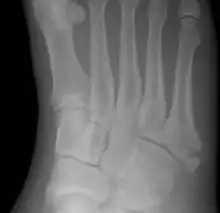

Jones fracture as seen on Xray

A person with a Jones fracture may not realize that a fracture has occurred. Diagnosis includes the palpation of an intact fibularis brevis tendon, and demonstration of local tenderness distal to the tuberosity of the fifth metatarsal, and localized over the shaft of the proximal metatarsal.

Diagnostic X-rays include anteroposterior, oblique, and lateral views and should be made with the foot in full flexion.